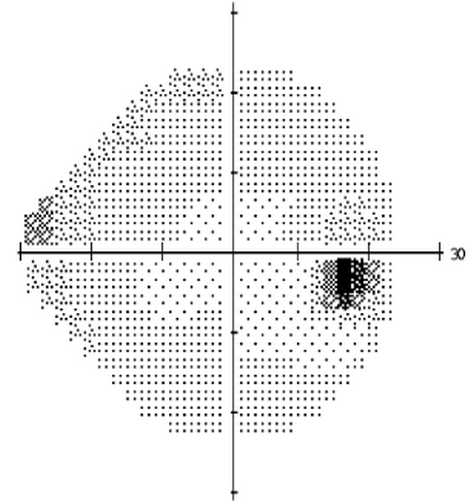

圖 | 正常人視野

圖 | 青光眼視野變化

視野是指人的頭部和眼球固定不動的情況下,眼睛觀看正前方物體時所能看得見的空間范圍(上述視野檢查圖中黑色部分表示視野缺損看不見)。